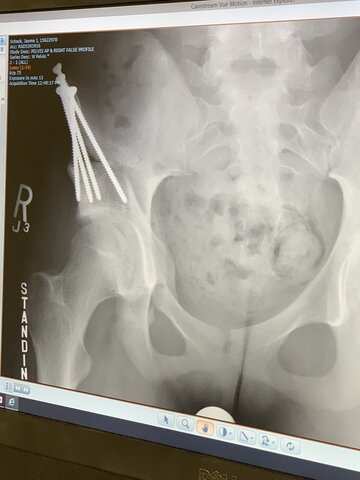

• Screws Removed

Screws Removed

I got my screws removed a couple days before coming to Drake University for my freshman year.